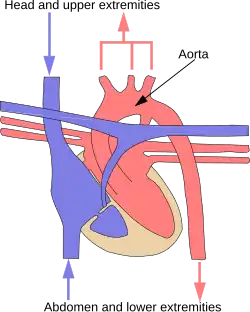

Большой (системный) круг кровообращения

Структура

Начинается из левого желудочка, выбрасывающего во время систолы кровь в аорту. От аорты отходят многочисленные артерии, в результате кровоток распределяется согласно сегментарному строению по сосудистым сетям, обеспечивая подачу кислорода и питательных веществ всем органам и тканям. Дальнейшее деление артерий происходит на артериолы и капилляры. Общая площадь поверхности всех капилляров в организме человека примерно 1500 м2[1]. Через тонкие стенки капилляров артериальная кровь отдаёт клеткам тела питательные вещества и кислород, а забирает от них углекислый газ и продукты метаболизма, попадает в венулы, становясь венозной. Венулы собираются в вены. К правому предсердию подходят две полые вены: верхняя и нижняя, которыми заканчивается большой круг кровообращения. Время прохождения крови по большому кругу кровообращения составляет 23—27 секунд.

Особенности кровотока

- Венозный отток от непарных органов брюшной полости осуществляется не напрямую в нижнюю полую вену, а через воротную вену (сформированную верхней, нижней брыжеечными и селезёночной венами). Воротная вена, войдя в ворота печени (отсюда и название) вместе с печёночной артерией, делится в печёночных балках на капиллярную сеть, где кровь очищается и только после этого по печёночным венам поступает в нижнюю полую вену.